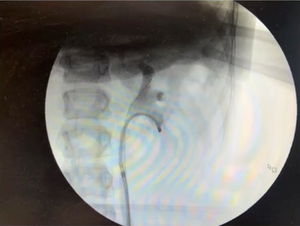

Pediatric ureteroscopy: Principles for safe surgery

Dr. Dangle shows that pediatric ureteroscopy is safe and feasible with good results and without long-term sequelae on the ureters.